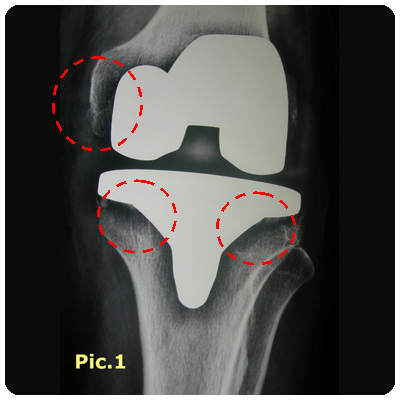

![]() Pain and discomfort from loose femur and tibial compenents (clickimage for enlarge view) | <Successful Revision Surgery (clickimage for enlarge view) |